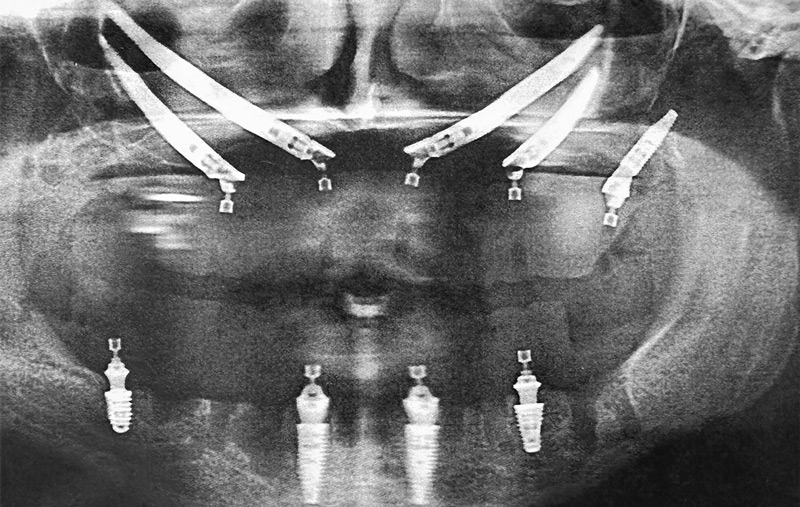

The zygoma, or cheekbone, is naturally dense and can serve as a strong anchor for dental implants. Unlike traditional implants that are inserted into the upper jawbone, zygomatic implants are placed into the cheekbone. These implants are specifically designed with longer posts that reach the zygoma and are positioned at an angle to ensure stability. By bonding with both the cheekbone and remaining jawbone, Zygomatic dental implants offer a reliable solution for individuals who have been told they lack sufficient jawbone density for regular implants.

For many patients with severe bone loss in the upper jaw, traditional dental implants require a bone graft before implant placement, which involves additional surgery, costs, and months of healing time. Zygomatic dental implants offer a faster, more efficient solution by eliminating the need for bone grafting. These implants don’t rely on the jawbone for support; instead, they are anchored into the dense cheekbone (zygoma), allowing for a secure and stable tooth restoration.